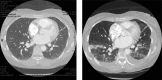

In spite of significant strides in the treatment of sickle cell disease (SCD), SCD crises are still responsible for high morbidity and early mortality. While most patients initially seek care in the acute setting for a seemingly uncomplicated pain episode (pain crisis or vaso-occlusive crisis), this initial event is the primary risk factor for potentially life-threatening complications. The pathophysiological basis of these illnesses is end-organ ischemia and infarction combined with the downstream effects of hemolysis that results from red blood cell sickling. These pathological changes can occur acutely and lead to a dramatic clinical presentation, but are frequently superimposed over a milieu of chronic vasculopathy, immune dysregulation, and decreased functional reserve. In the lungs, acute chest syndrome is a particularly ominous lung injury syndrome with a complex pathogenesis and potentially devastating sequelae, but all organ systems can be affected. It is, therefore, critical to understand the SCD patients' susceptibility to acute complications and their risk factors so that they can be recognized promptly and managed effectively. Blood transfusions remain the mainstay of therapy for all severe acute crises. Recommendations and indications for the safest and most efficient implementation of transfusion strategies in the critical care setting are therefore presented and discussed, together with their pitfalls and potential future therapeutic alternatives. In particular, the importance of extended phenotypic red blood cell matching cannot be overemphasized, due to the high prevalence of severe complications from red cell alloimmunization in SCD.